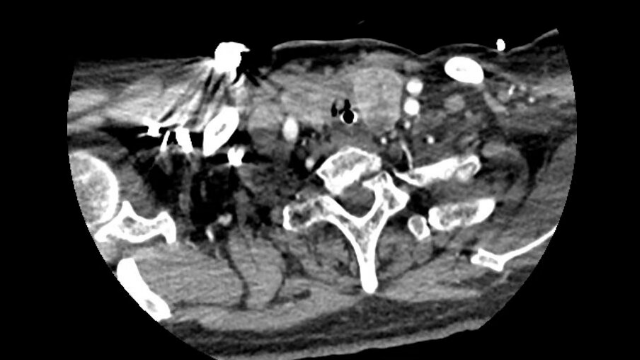

患者术前MR与病理信息

马利民、成兵团队术前依据患者的前列腺MR结果精准定位病灶,围绕病灶勾画出布针靶区,结合了超声的实时性和MR的高对比度的优势,术中根据术前已画出的病灶范围精心实施布针方案,大大减少了手术时长。

术前依据前列腺MRI结果精准定位病灶